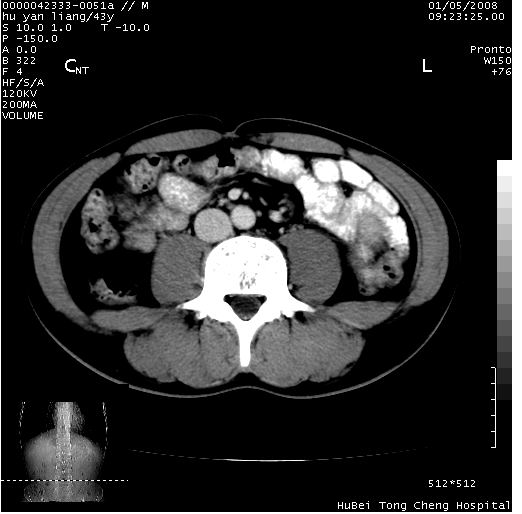

患者 男,43岁。右上腹不适1年余。既往有“肝右叶肝脓肿”病史,经保守治疗后痊愈。

b超提示:1)肝右叶肝内胆管结石。2)肝右叶占位性病变待排。

上中腹部ct轴位平扫+增强扫描(层厚10mm,螺距1.0,重建间隔10mm),图像如下:

肝右上叶偏后方较大团片状钙化灶,支持:肝脓肿后遗改变!

肝右叶后段团块状钙化灶,结合病史考虑肝脓肿痊愈后表现。